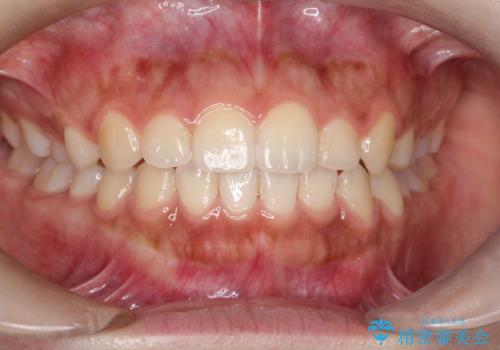

気になる八重歯を治したい ワイヤー装置での抜歯矯正

前歯のデコボコと突出感 インビザラインで改善

どんなに磨いても汚れが溜まる 抜歯矯正で清潔な口元に

口元をスッキリと ワイヤーでの抜歯矯正

前歯の咬み合わせとデコボコを解消 インビザラインによる矯正治療